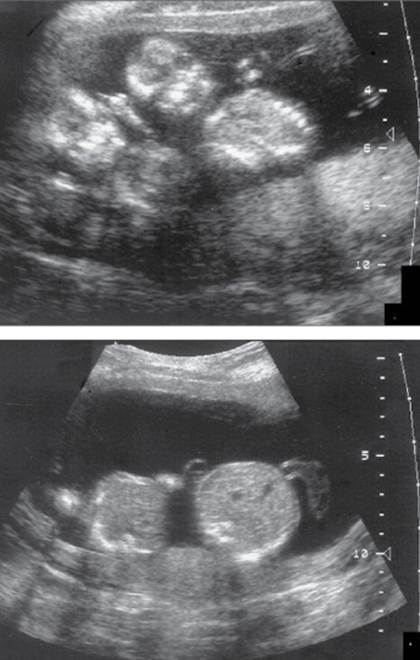

Poli-Oli sequence (stuck twin)

Fetus papyraceous